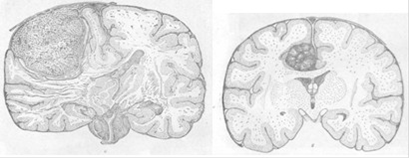

Менингиомы. [ 2]

а) конвекситальная полушария мозга; б) парасагиттальная в глубине межполушарной щели.

[2] Ангиоретикулема червя мозжечка.